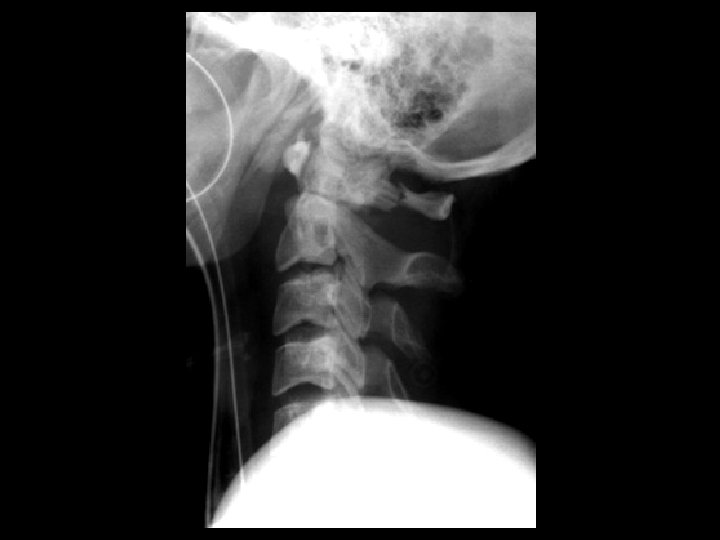

Bilateral jumped facets • Findings: – complete anterior dislocation of C 5 on C 6 – locked bilateral facets – disruption of ALL & PLL – “bat wing” appearance – mechanism: extreme hyperflexion – UNSTABLE